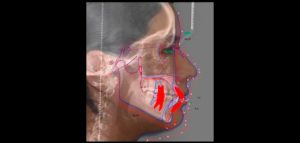

La evaluación y comprensión de los movimientos de la articulación temporomandibular (ATM) y su activación son importantes para determinar las causas de la falta de